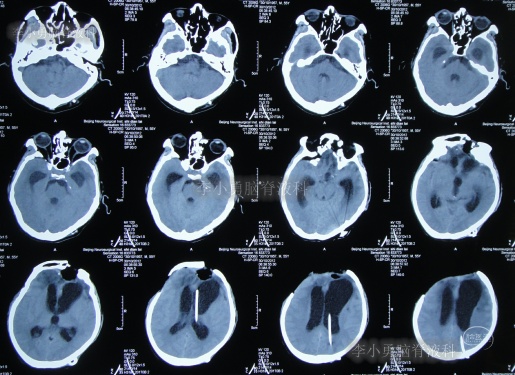

第3家医院出院后26天即2012年9月26日(开颅术后92天),因患者失语、嗜睡、吞咽障碍,第2次住入第3家医院,入院后2天即2012年9月28日,给予伤口及脑内脓肿清创缝合术+脑脊液漏修补术+右大腿取脂肪术,但术后2周即2012年10月12日,复查头颅CT提示脑积水(图-1)。

图-1:2012年10月12日头颅CT

2012年10月16日(第3家医院第2次住院20天),进行了脑室腹腔分流术(图-2)。

图-2:2012年10月16日头颅CT

脑室腹腔分流术后7天即2012年10月23日,患者突发意识丧失、双眼上翻伴头部抖动近20分钟后自行缓解,查头颅CT(图-3)后考虑为“颅内感染”。

图-3:2012年10月23日头颅CT

脑室腹腔分流术后11天即2012年10月27日,进行了脑室腹腔分流管腹腔端外置术(图-4),术中可见清亮脑脊液流出。

图-4:2012年10月27日头颅CT

治疗期间给予腰穿脑脊液检查未见细菌,但白细胞、蛋白偏高,体温仍间断升高,最高38.6度,期间查头颅CT示脑室仍有扩张(图-5)。

图-5:2012年10月30日头颅CT